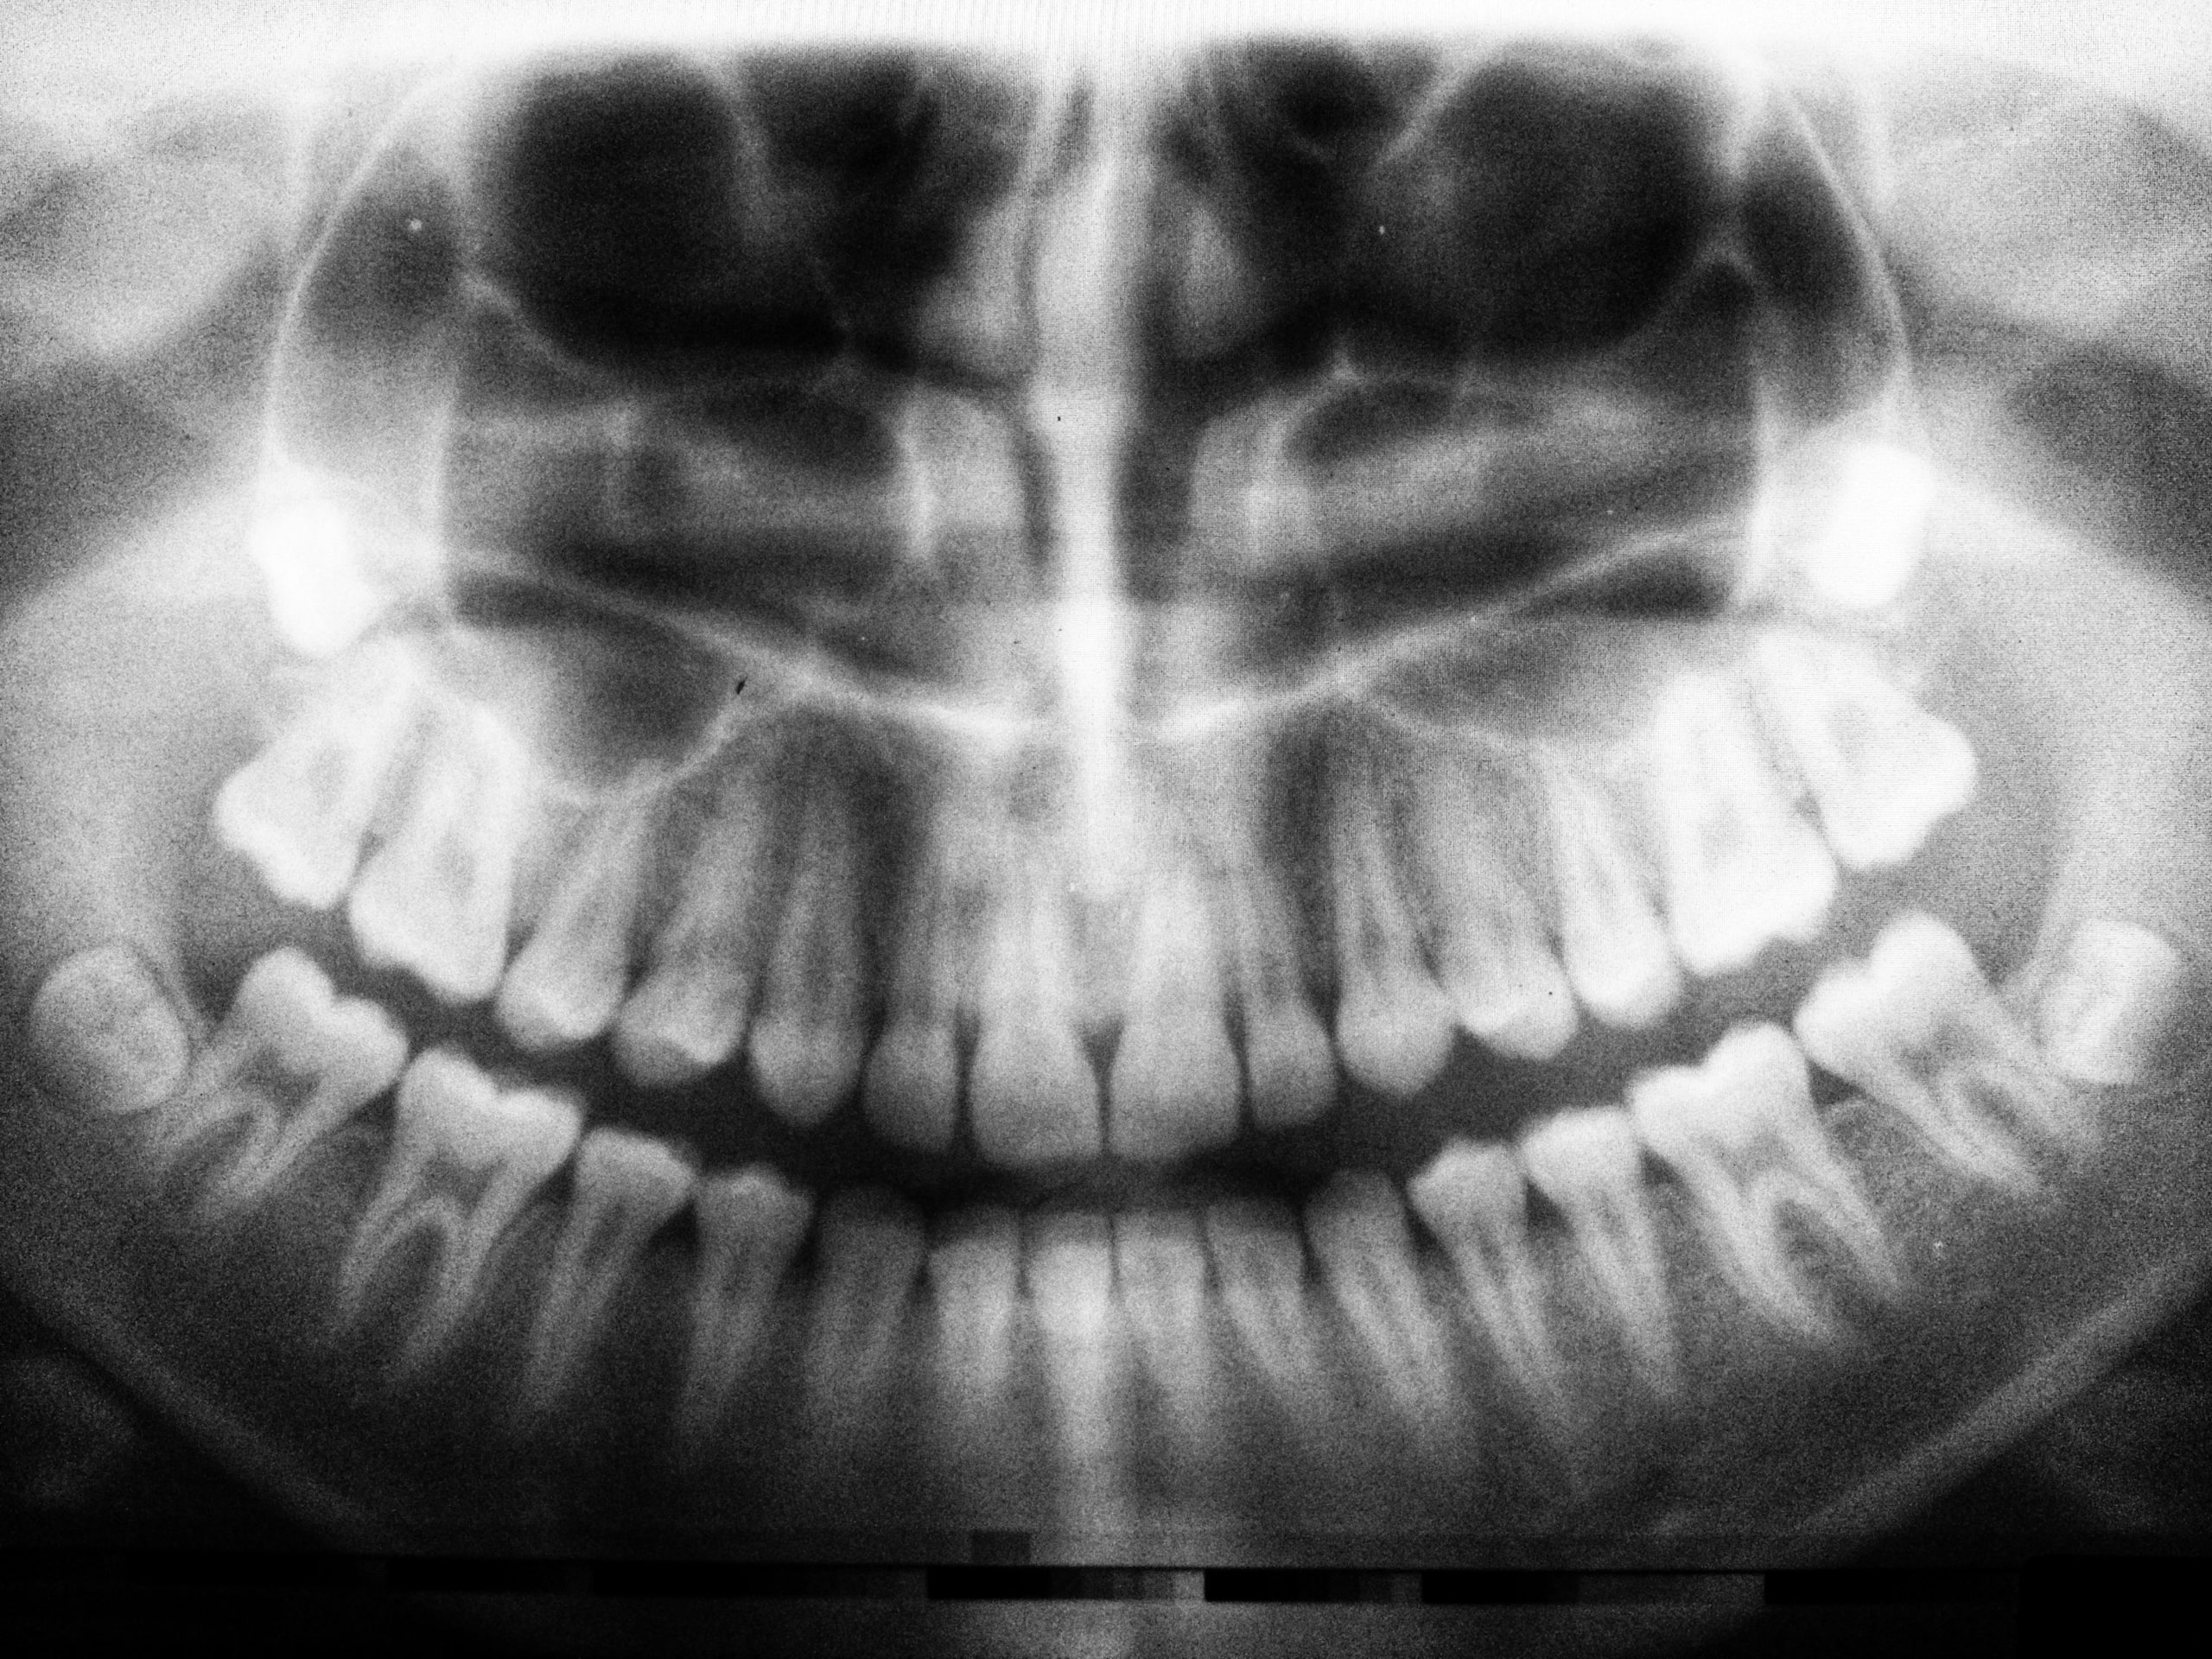

Digital X-Rays

We want your experience with us to be as comfortable as possible at every stage of your dental treatment, beginning with a professional evaluation and expert diagnosis. In addition to standard digital x-rays, we utilize extraoral bitewing x-rays that don’t require a sensor to be placed in your mouth.